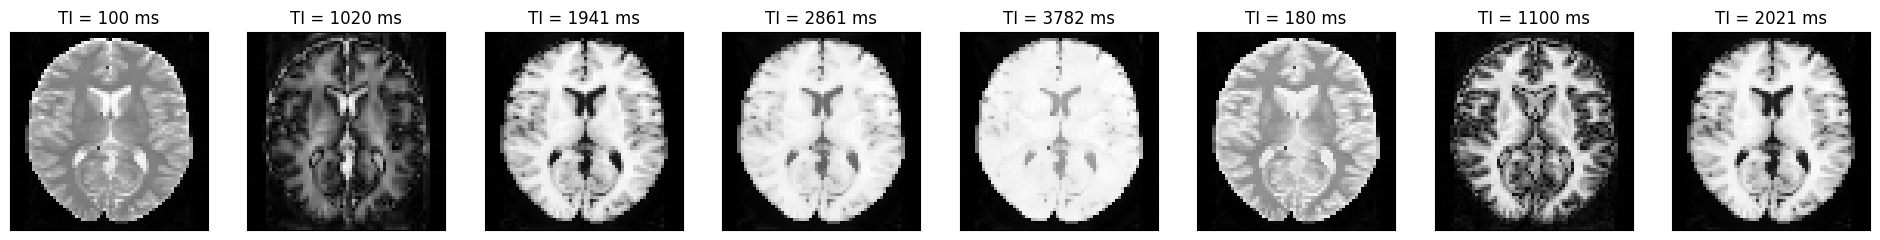

We can now plot the images at different inversion times.

idat = idata.rss().abs().numpy().squeeze()

acquisition_time_stamp = idata.header.acquisition_time_stamp.squeeze()

ti = np.concatenate(

(

idata.header.ti[0] + acquisition_time_stamp[:5] - acquisition_time_stamp[0],

idata.header.ti[1] + acquisition_time_stamp[5:] - acquisition_time_stamp[5],

)

fig, ax = plt.subplots(1, idat.shape[0], figsize=(3 * idata.shape[0], 3))

for i in range(idat.shape[0]):

ax[i].imshow(idat[i, :, :], cmap='gray')

ax[i].set_title(f'TI = {int(np.round(ti[i] * 1000))} ms')

ax[i].set_xticks([])

ax[i].set_yticks([])